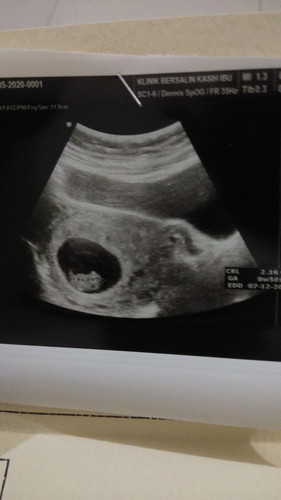

7minggu sempet usg yg terlihat hanya penebalan didning rahim,,saking penasarannya 9minggu balik lagi k dr kandungan dan puji syukur alhamdulillah janin aku udh kelihatan semoga sehat terus smpai persalinan nanti aamiin??